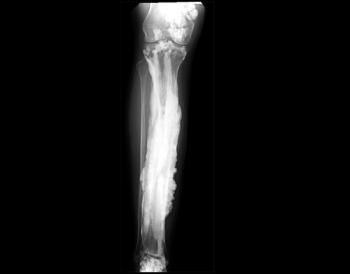

National Institutes of Health researchers have uncovered a genetic basis of a rare bone disease known as melorheostosis and said the discovery could offer potential treatment targets, provide clues about bone development, and lead to insights about fracture healing and osteoporosis.